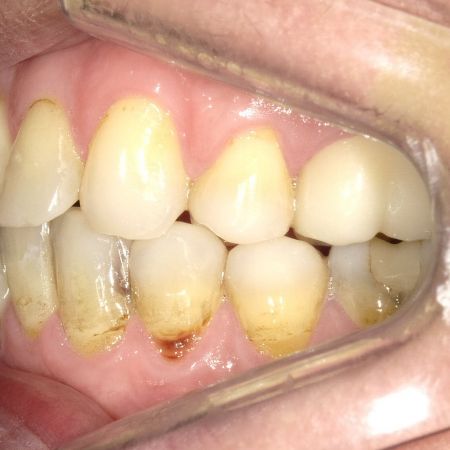

Links Zustand beim Einsetzen der festen Zahnspange, rechts Situation unmittelbar nach der Operation (nach 2 Jahren, 4 Monaten). Der Unterkiefer wurde chirurgisch vorgesetzt und dadurch die Zahnreihen besser in Kontakt gebracht. Die Operation wurde an der Uniklinik Homburg durchgeführt. Eine Feineinstellung der Verzahnung ist aber im Laufe der kieferorthopädischen Nachbehandlung noch erforderlich.